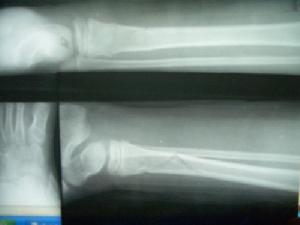

Kalamchi等依照臨床與X線表現,將其分成三種類型。Ⅰ型為脛骨完全缺如,主要表現為小腿短縮及彎曲畸形;偶有足內側列的跖跗骨缺如,膝關節屈曲攣縮,腓骨頭上移和股骨遠端發育不良;Ⅱ型為脛骨遠端1/2缺如,脛骨近端和股骨遠端發育較好,因此保留了膝關節功能。但有腓骨近端後移和膝關節輕度屈曲攣縮;Ⅲ型只有脛骨遠端發育不良,以下脛腓關節分離、足內翻和外踝突出為特徵。

本病X線表現具有特徵性,即脛骨在不同部位的缺如,比較容易做出正確診斷。但對脛骨遠端缺如者,在嬰兒期需要與先天性馬蹄內翻足鑑別。